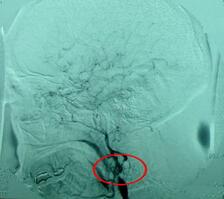

在大鼠大脑中动脉阻塞模型中,与生理盐水灌注相比较,非离子型、低渗碘海醇对比剂颈内动脉灌注增加颅内出血风险。与低渗碘帕醇和生理盐水相比较,等渗碘克沙醇(290 mOsm/kg H2O)灌注显示较小的梗死与较少的颅内出血。据研究人员了解,尚无研究比较在人的卒中中碘化X线对比剂的差异。本研究推测,在卒中介入治疗III期试验(IMS III)中,与碘克沙醇相比,低渗对比剂与疾病结局恶化相关。研究结果显示,对于血管内治疗的M1段闭塞5个预先设定的疗效和安全性终点,相对风险评估对碘克沙醇有利。相关报告2015年7月发表在《AJNR Am J Neuroradiol》。 在该项研究中,对于133例接受血管内治疗的M1段闭塞患者,研究人员前瞻性评估碘化X线对比剂数据。在接受碘克沙醇(n = 31)或低渗对比剂(n = 102)的患者中,研究人员比较了5项预先设定的疗效和安全性终点(mRS 0-2结局、改良的TICI 2b-3再灌注、无症状性和有症状性颅内出血及死亡率)。碘化X线对比剂类型间的变量失衡或与结局的关联被认为是校正模型潜在的协变量。除碘化X线对比剂类型外,最终的协变量在逻辑回归模型中使用分段法选定。使用log-link回归模型评估校正相对风险。 结果显示,基线或血管内治疗变量可能与结局潜在相关,既往抗血小板药使用较常见,微导管碘化X线对比剂碘克沙醇注射较少。对于M1段闭塞5个预先设定的终点,相对风险评估对碘克沙醇有利。碘克沙醇微导管注射的风险差异百分比在数字上较大。 结果表明,尽管数据有利于等渗碘克沙醇对比剂用于M1段闭塞再灌注不是定论,但潜在的病理生理机制显示需要进一步研究其临床获益。 (环球医学资讯供稿 责任编辑 :Ada) 参考资料:http://www.ncbi.nlm.nih.gov/pubmed/26228892